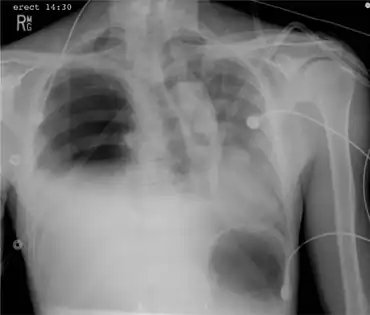

Portable chest x-ray demonstrating a right-sided tension hemopneumothorax